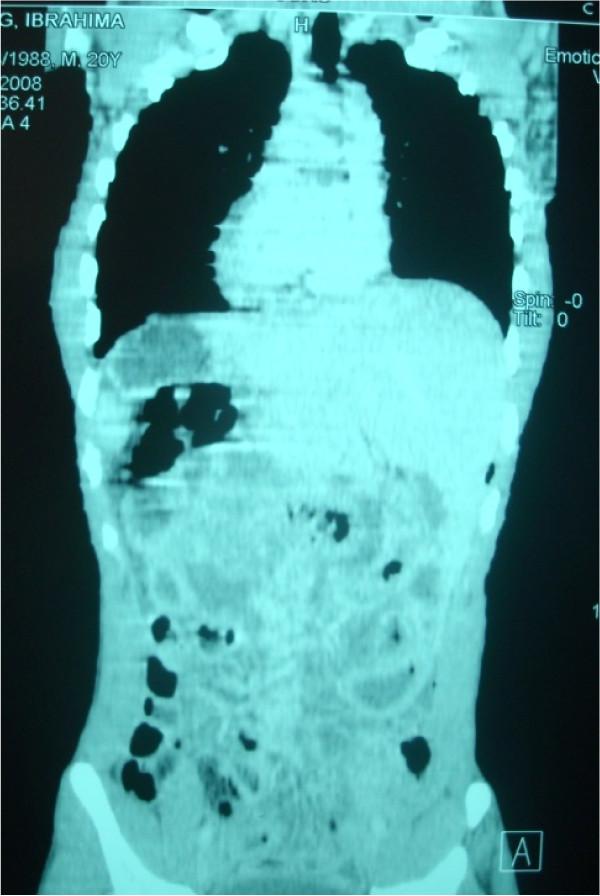

We report the case of a 20-year-old African man who presented to the emergency department with a 4-day history of diffuse abdominal pain, which began in his left iliac region and hypogastrium. After examination, we initiated a surgical exploration for peritonitis. We discovered a situs inversus at the left side of his liver, and his appendix was perforated in its middle third. A complementary post-operative thoracic and abdominal tomodensitometry revealed a situs inversus totalis.

我们报告一例20岁非洲男性病例,该患者因弥漫性腹痛4天就诊于急诊科,腹痛始于左髂区和下腹部。检查后,我们因腹膜炎进行了手术探查。我们发现其肝脏位于左侧,存在内脏反位,且阑尾在其中段三分之一处穿孔。术后补充的胸部和腹部体层摄影术显示为完全性内脏反位。